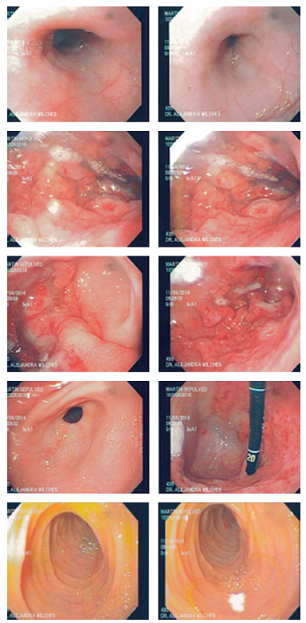

Finalmente, se interconsultó a gastropediatría al sexto día de hospitalización y se ordenó una endoscopia digestiva superior (EDS) y colonoscopia por la sospecha de gastropatía y/o enteropatía perdedora de proteína. Se encontraron pliegues corporales hipertróficos, erosionados y con mucosa friable, mucosa antral de aspecto normal y mucosa fúndica con erosiones superficiales, por lo que se sospechó EM (Figura 1). Con estos hallazgos se mantiene una conducta expectante con respecto a la realización de colonoscopia.

En el estudio anatomopatológico se encontró esofagitis leve, gastropatia hipertrófica (hiperplasia foveolar, dilatación y atrofia de glándulas, aumento de fibras musculares en la lámina propia, sin Helicobacter pylori) y signos de duodenitis crónica, hallazgos que confirmaron el diagnóstico de EM (Figura 2).